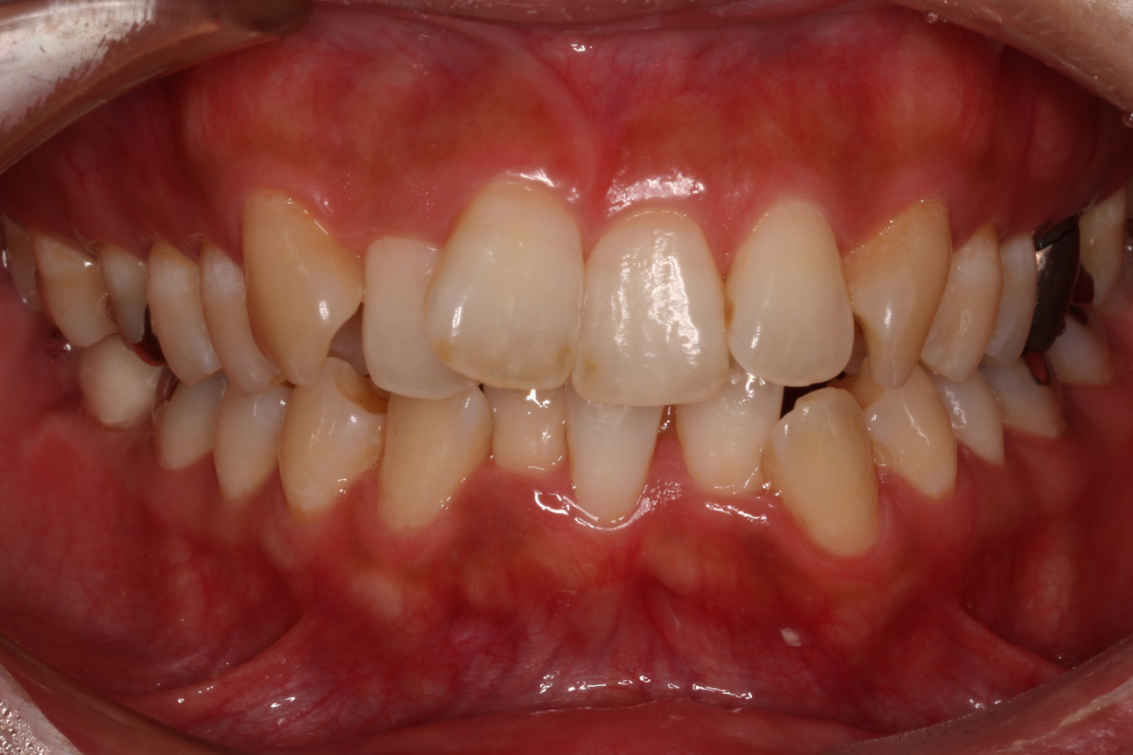

矯正治療の症例紹介

- 患者様情報30代 女性

- 来院動機歯並びが気になる

- 治療内容矯正治療

- 治療期間約2年

- 治療費用1,109,900円(税込)

検査費、治療費、月々の調整費込 - 治療のリスク歯肉退縮の可能性がある、装置装着の痛みを感じる場合がある